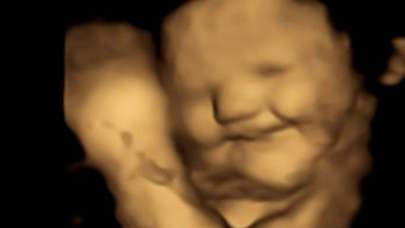

Bebekler, anne karnında yemek seçiyor! Lahanayı gören fetüsün yüzünü ekşitmesi gündem oldu!

3 yıl önce